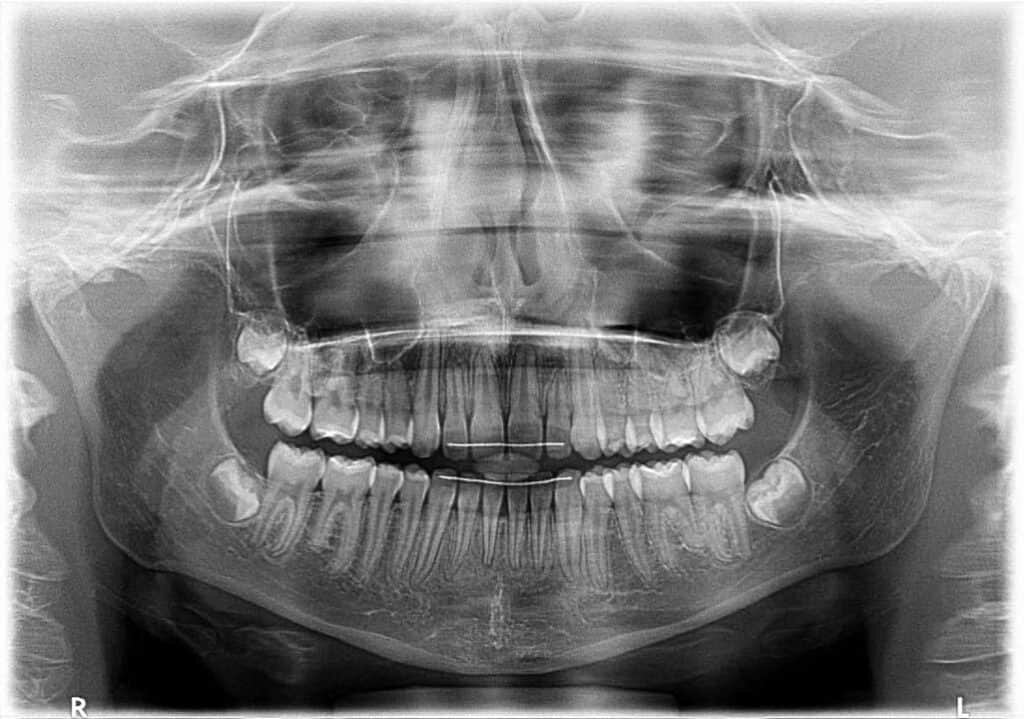

L’ortopantomografia (o "panoramica dentale") è un esame radiografico che consente di studiare le arcate dentarie superiori e inferiori.

L’ortopantomografia (OPT) o panoramica dentale, è un esame radiografico che viene effettuato mediante un'apparecchiatura chiamata ortopantomografo e consente allo specialista di studiare le arcate dentarie superiori e inferiori.

Fornisce una visione dell’apparato dento-parodontale nel suo insieme: consente infatti di evidenziare su un’unica pellicola entrambi i mascellari, i processi alveolari e le articolazioni temporo-mandibolari.

Inoltre fornisce informazioni relative ad anomalie di numero, di sviluppo, di forma e di sede dei denti, permettendo di esaminare la situazione del paziente all’inizio del trattamento, nelle fasi intermedie e in quelle finali.